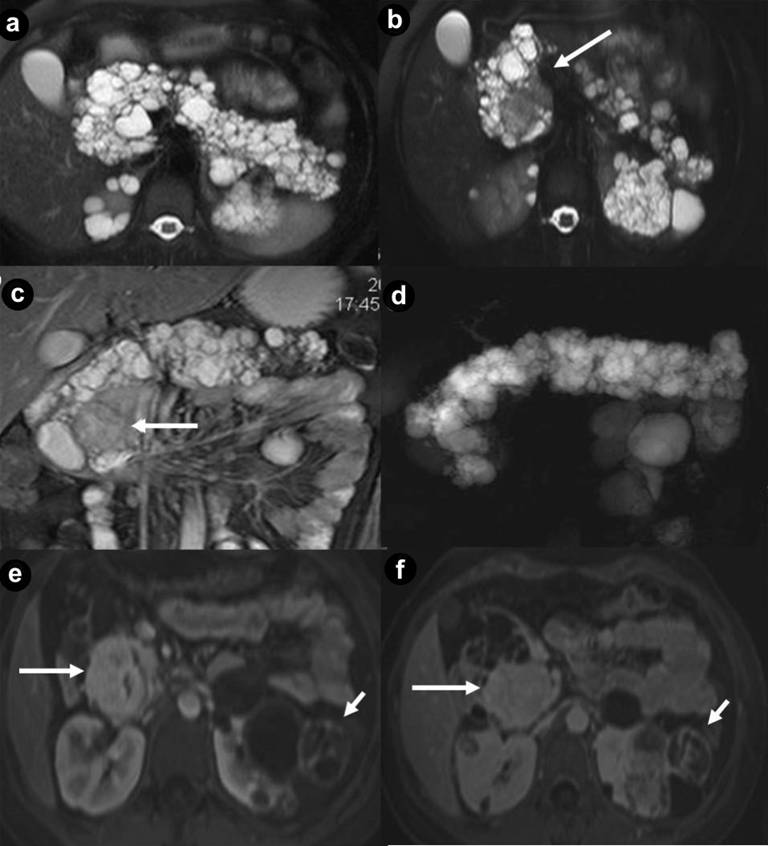

Figure 6. Pancreatic diffuse cystic non functioning neuroendocrine tumor. A 43-year-old woman affected by VHL disease. Axial T2-weighted MR images (a.) and 3D volumetric gradient-echo T1-weighted fat suppressed images after intravenous contrast medium administration during arterial pancreatic (b.), portal venous (c.) and delayed (d.) phases of contrastographic dynamic study. Pancreatic gland is enlarged and parenchyma is thickened, completely replaced by multiple, lobulated fluid cysts, the largest in pancreatic head and tail (arrows), hyperintense in T2-weighted MR images, with thickened walls and irregular septa. Multiple small parenchymal nodules (small arrows), hyperintense on T2-weighted MR images but with lower signal intensity compared to fluid lesions, are visible in pancreatic body-tail and head. After intravenous contrast medium administration during arterial pancreatic (b.), portal venous (c.) and delayed phases (d.) walls and septa of cystic lesions show enhancement. Also multiple, small, solid parenchymal nodules enhance during pancreatic phase of dynamic MR study (short arrows). A large fluid cystic lesion in pancreatic head causes stenosis of main pancreatic duct and upstream duct dilatation (arrowhead). Total pancreatectomy and retroperitoneal lymphadenectomy was performed. Histological specimen showed the presence of pancreatic diffuse non functioning neuroendocrine carcinoma with malignant cystic and solid lesions. Retroperitoneal adenopathy metastasis were present. |

Figure 7. Renal cysts and cystic renal cell carcinoma. A 43-year-old man with VHL disease. Coronal (a. b.) and axial (c.) T2-weighted MR images; axial (d.) and coronal (e. f.) 3D volumetric gradient-echo T1-weighted fat suppressed images after intravenous contrast medium administration during arterial (d. e.) and venous (f.) phases of contrastographic dynamic study. Multiple and bilateral simple, fluid renal cysts, with high signal intensity on the T2-weighted images (a. b. c.) and hypointense without enhancement after intravenous contrast medium administration during arterial (d. e.) and venous (f.) phases. In the lower pole of the left kidney a complex cystic mass (arrows) is present, with heterogeneous hyperintensity on the T2-weighted images, septa and solid areas enhanced after intravenous contrast medium administration during arterial (d. e.) and venous (f.) phases. Surgical enucleation of left renal lesion was performed. Histological specimen showed the presence of a cystic renal cell carcinoma.

Thirty-four pancreatic lesions were found in the 23 patients. In qualitative analysis, the MR imaging findings were: 6 (26.1%) unilocular fluid cystic lesions (Figure 1abc): 3 (13.0%) in pancreatic head, 3 (13.0%) in pancreatic body-tail; 11 (47.8%) serous micro- or micro/macro-cystic cystadenomas (Figures 1def, 4, and 5): 1 (4.3%) in pancreatic head, 2 (8.7%) in pancreatic body-tail (Figure 1), 8 (34.8%) diffuse (Figures 4 and 5); 8 (34.8%) neuroendocrine solid tumors: all of them non-functioning NET and hypervascular during arterial pancreatic phase of contrastographic dynamic study (Figures 2, 3, 4, and 5), 4 (17.4%) at pancreatic head (Figures 2ab; 3ace, and 4), 4 (17.4%) at pancreatic body-tail (Figures 2cd and 5); 1 (4.3%) cystic non-functioning NET, diffuse in all pancreatic gland (Figure 6); in 4 (17.4%) cases association of non-functioning NET and pancreatic cystic lesions (3 cases of association of non-functioning NET and serous cystadenoma (13.0%); 1 case of association of non-functioning NET and pancreatic simple cystic lesion (4.3%)) were present (Figures 4 and 5). Vascular invasion was not detected in any patients.

At MR imaging [3, 4, 9, 15, 16, 38, 39, 40] they result hypointense on T1-weighted images, and hyperintense on T2-weighted images (Figures 4ab, 5a, and 7abc), with no walls enhancement after intravenous gadolinium contrast medium administration (Figures 5def and 7def).

According to the literature, in our series simple renal cysts were present in 78.3% of patients. In 69.6% of our cases they were multiple and bilateral (Figures 4ab, 5, and 7).

Complex cysts were present in 56.5% of VHL patients (Figures 1a and 2b). The average maximum diameter of lesions was 50.5 mm in simple cysts and 60 mm in complex cysts.

MR findings [3, 9, 15, 16, 38] of renal carcinoma in patients with VHL syndrome are low signal intensity at T1-weighted images and high signal intensity at T2-weighted images, hypervascular with enhancement during arterial phase of contrastographic dynamic study, hypointense with wash-out in venous phase solid mass. The hypervascularity of renal lesions is probably related to increased levels of vascular endothelial growth factors, and other angiogenic factors produced by these hereditary tumors [41, 42].

Frequently, renal carcinoma in patients with VHL syndrome may present as complex cystic masses [15, 19] with fluid component, mural nodules, thick walls and septa showing enhancement on T1-weighted images after intravenous gadolinium contrast medium administration (Figures 4ef and 7bcdef). Malignant complex cysts may show a low-signal intensity walls on T2-weighted images (pseudocapsule).

Cystic renal cells carcinoma or malignant complex cysts were present in 13.0% of VHL patients (Figures 4ef and 7bcdef).